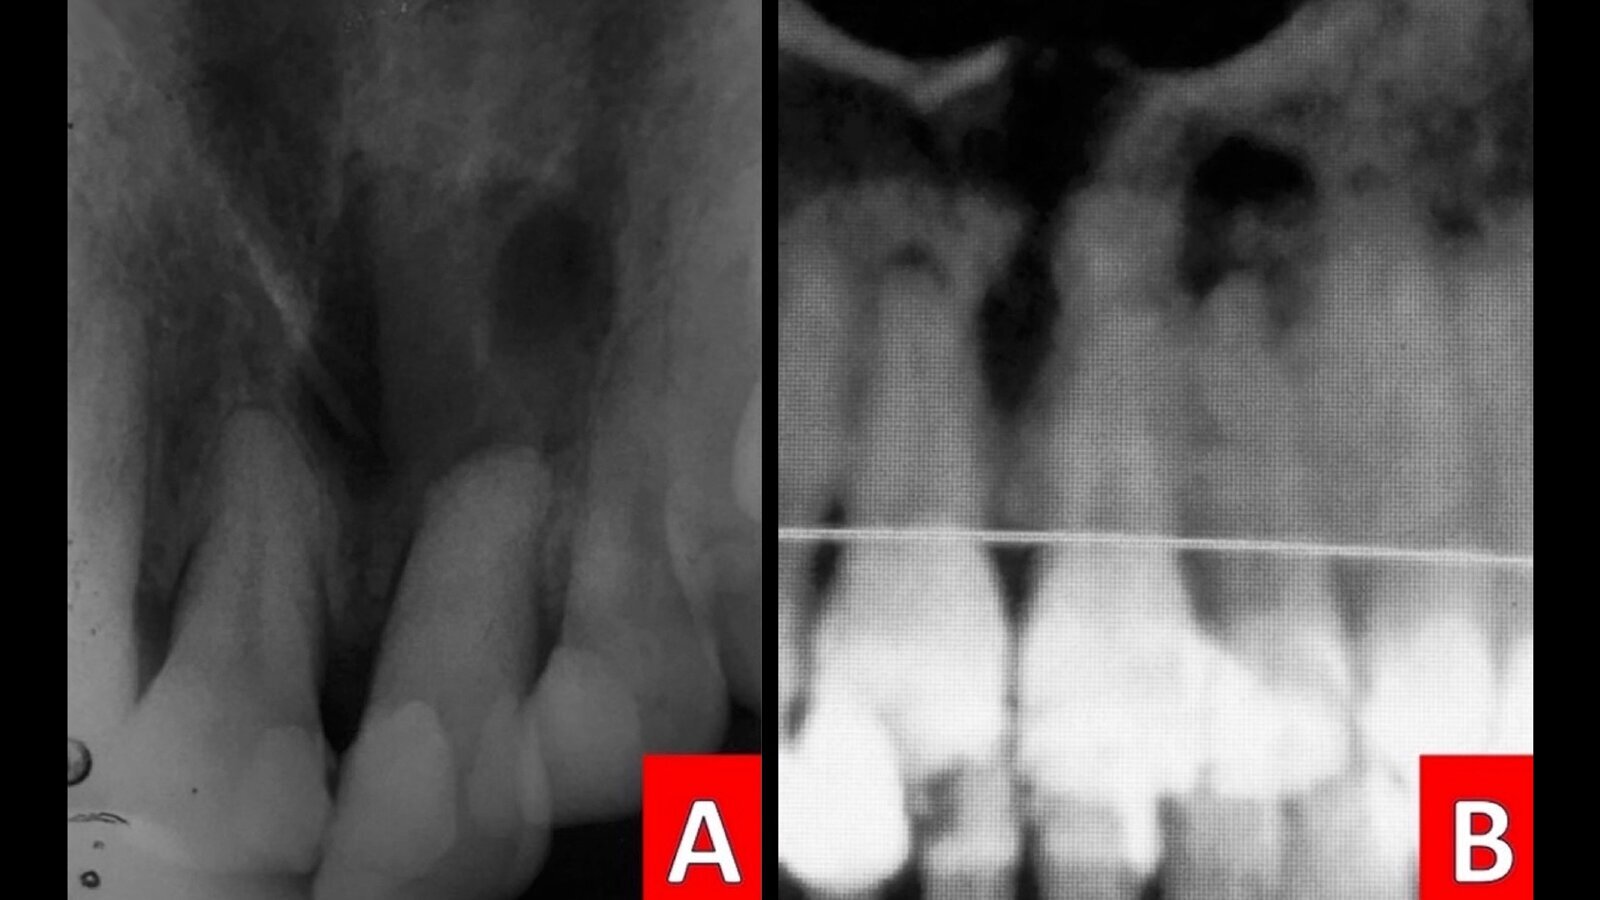

Figura 1. A) Radiografía periapical inicial. B) Imagen de contraste en TAC de frente.

Se presentó un paciente de 37 años, sexo femenino. El motivo de la consulta referido es: “Ligero dolor e inflamación en la encía por un golpe en el diente hace seis meses”. No refiere ningún síndrome, enfermedad o patología sistémica, ni medicación actual; es una paciente que responde con actitud colaboradora. En el examen clínico intraoral se observa una dentición permanente con tejidos blandos normales, restauraciones metálicas y estéticas sin desajuste. Falta de cordales (refiriendo esta ausencia por extracción previa a tratamiento ortodóntico, finalizado cuatro años antes). A la exploración, el diente 22 presenta una restauración mesio-palatina con composite y fractura del esmalte en el tercio incisal distal de la corona y fracturas verticales perceptibles al método de transiluminación. En el fondo del saco la paciente refiere ligero malestar a la digito-palpación. Se tomo una radiografía periapical inicial en la que se observa radiolucidez difusa y no definida en el periápice (Figura 1). Para una minuciosa observación adicional y como soporte de la planeación endo-quirúrgica, se solicitó un TAC, observando en la cita subsecuente mediante contrastes específicos la zona perirradicular, apreciando el alcance de la lesión y las estructuras involucradas (Figura 1). En la revisión de este mismo estudio, en el cuerpo mandibular también se localizaron dos dientes supernumerarios; ubicados en la línea media, uno en posición transversa, distoposterior, y el otro en orientación vertical, hacia distal, comprometiendo el conjunto de dientes anteriores inferiores. (Figura 2)